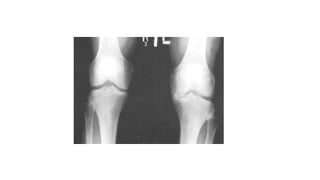

Caso Clínico 2 •Arco de movimento (ADM) encontra-se diminuído moderadamente a direita, com crepitação presente.

A-DIMINUIÇÃO DO ESPAÇOARTICULAR EM PLATÔ MEDIAL B -VISÃO AMPLIADA DO JOELHO DIREITO